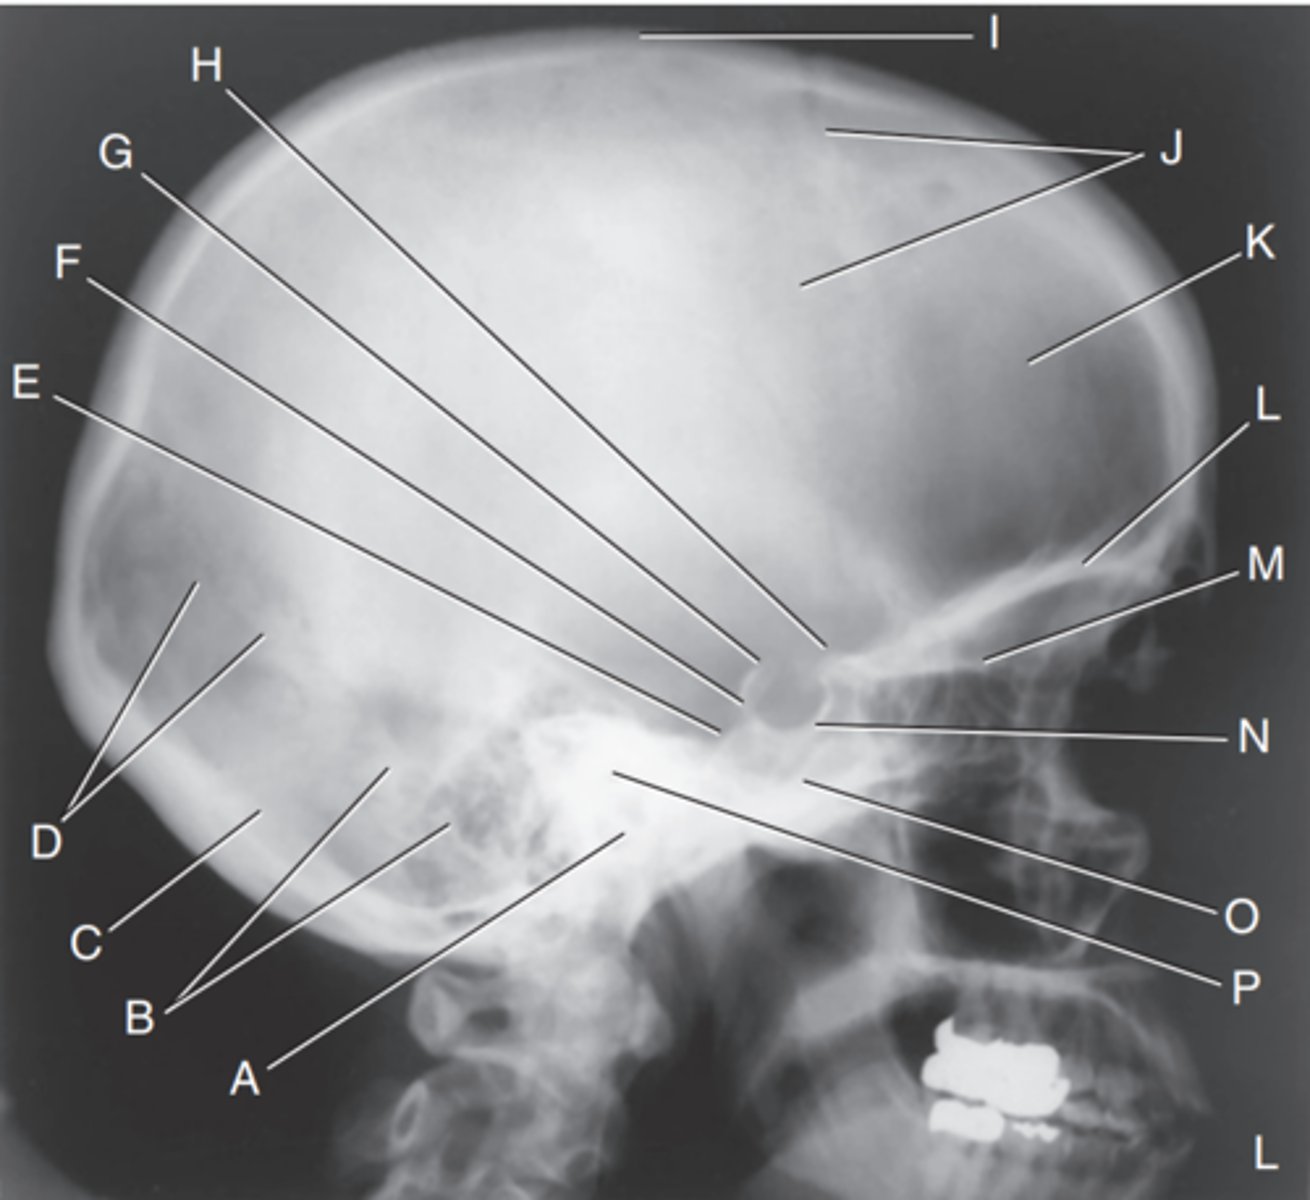

EAM

Label A

Mastoid portion of temporal bone

Label B

Occipital bone

Label C

Lambdoidal suture

Label D

Clivus

Label E

Dorsum sellae

Label F

Posterior clinoid processes

Label G

Anterior clinoid processes

Label H

Vertex of cranium

Label I

Coronal suture

Label J

Frontal bone

Label K

Orbital plates

label L

Cribriform plate

Label M

Sella turcica

Label N

Body of sphenoid (sphenoid sinus)

Label O

Petrous portion of temporal bone

Label P